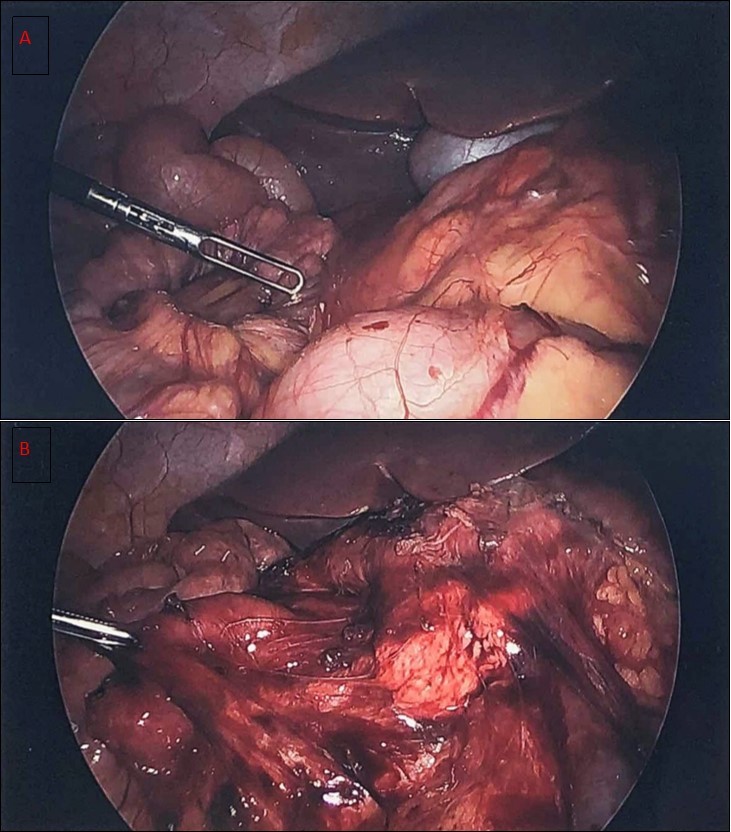

A diagnostic laparoscopy was done showing malrotation with Ladd’s bands constricting the duodenum. Laparoscopic Ladd’s procedure was performed (Figure 3). A three port technique was used. Harmonic scalpel ™ (Ethicon Endosurgery) was used as the energy source to divide the bands. The appendix/cecum that was located in the midline suprapubic area was mobilized by continuing to divide abnormal mesenteric attachments and appendectomy was performed. At completion, small bowel was positioned to the right and large bowel positioned to the left. The duration of surgery was around 100 minutes. Patient had uneventful postoperative course and was discharged on postoperative day 2

Figure 3.a) diagnostic laparoscopy showing Ladd’s bands b) liberation of the duodenum after the Ladd’s procedure with the small bowel to the right of the abdomen